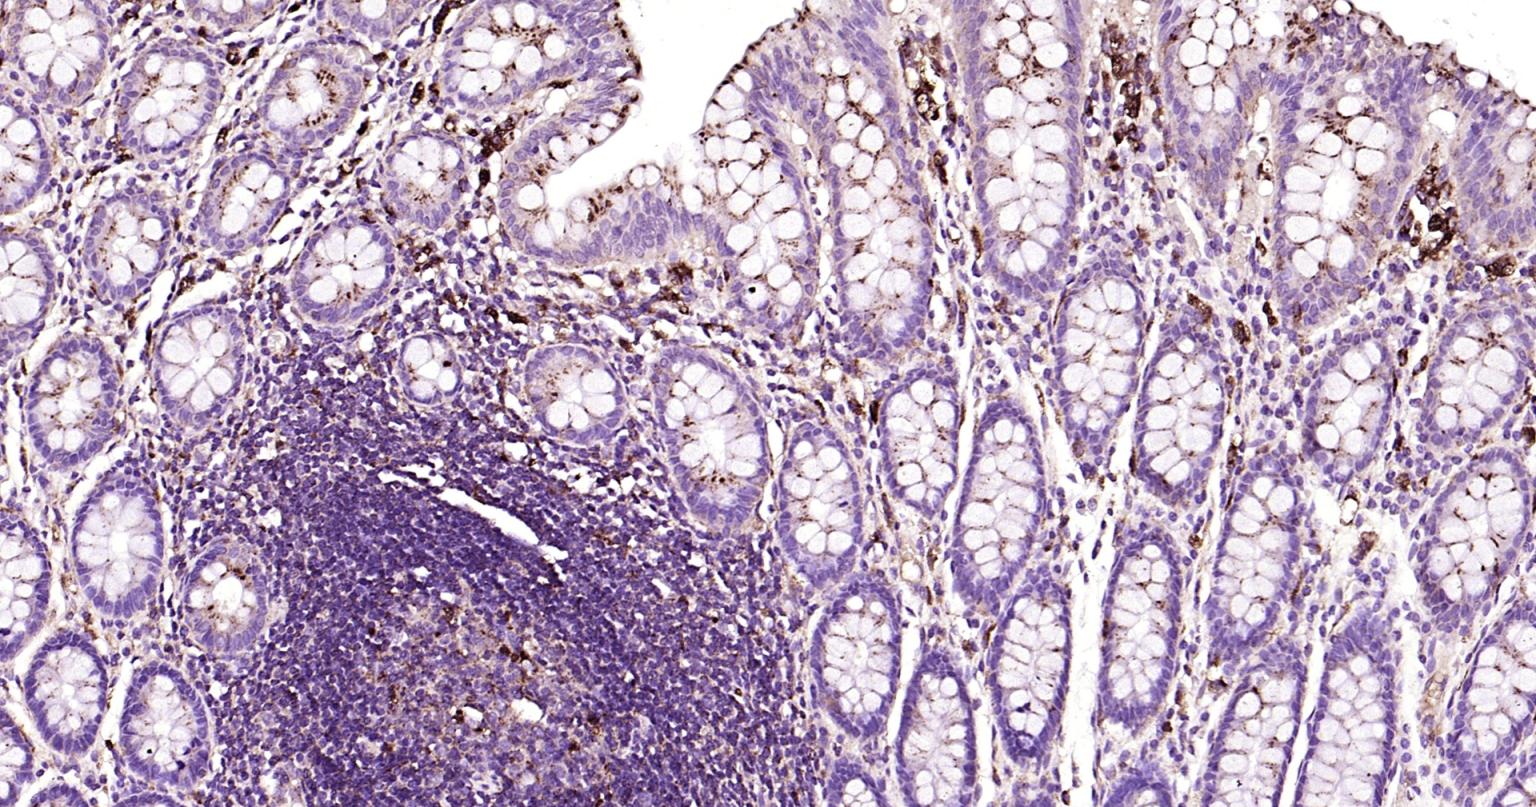

| IHC-P | Human | 1:100-500 | |